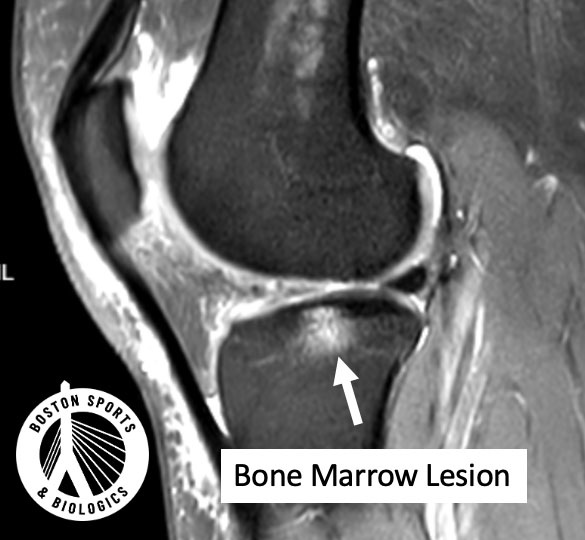

On MRI, a bone marrow lesion appears as an ill-defined bright area in the bone just beneath the cartilage (the subchondral bone). Historically, this was called “bone marrow edema,” implying simple swelling. But research shows it’s more complex than that. Learn more about knee osteoarthritis here.

A landmark MRI–histology study by Zanetti et al. in Radiology found that what we call “bone marrow edema” on MRI is often not primarily fluid. Instead, it commonly contains:

In other words, a BML represents stressed, injured, and actively remodeling bone, not just inflammation.